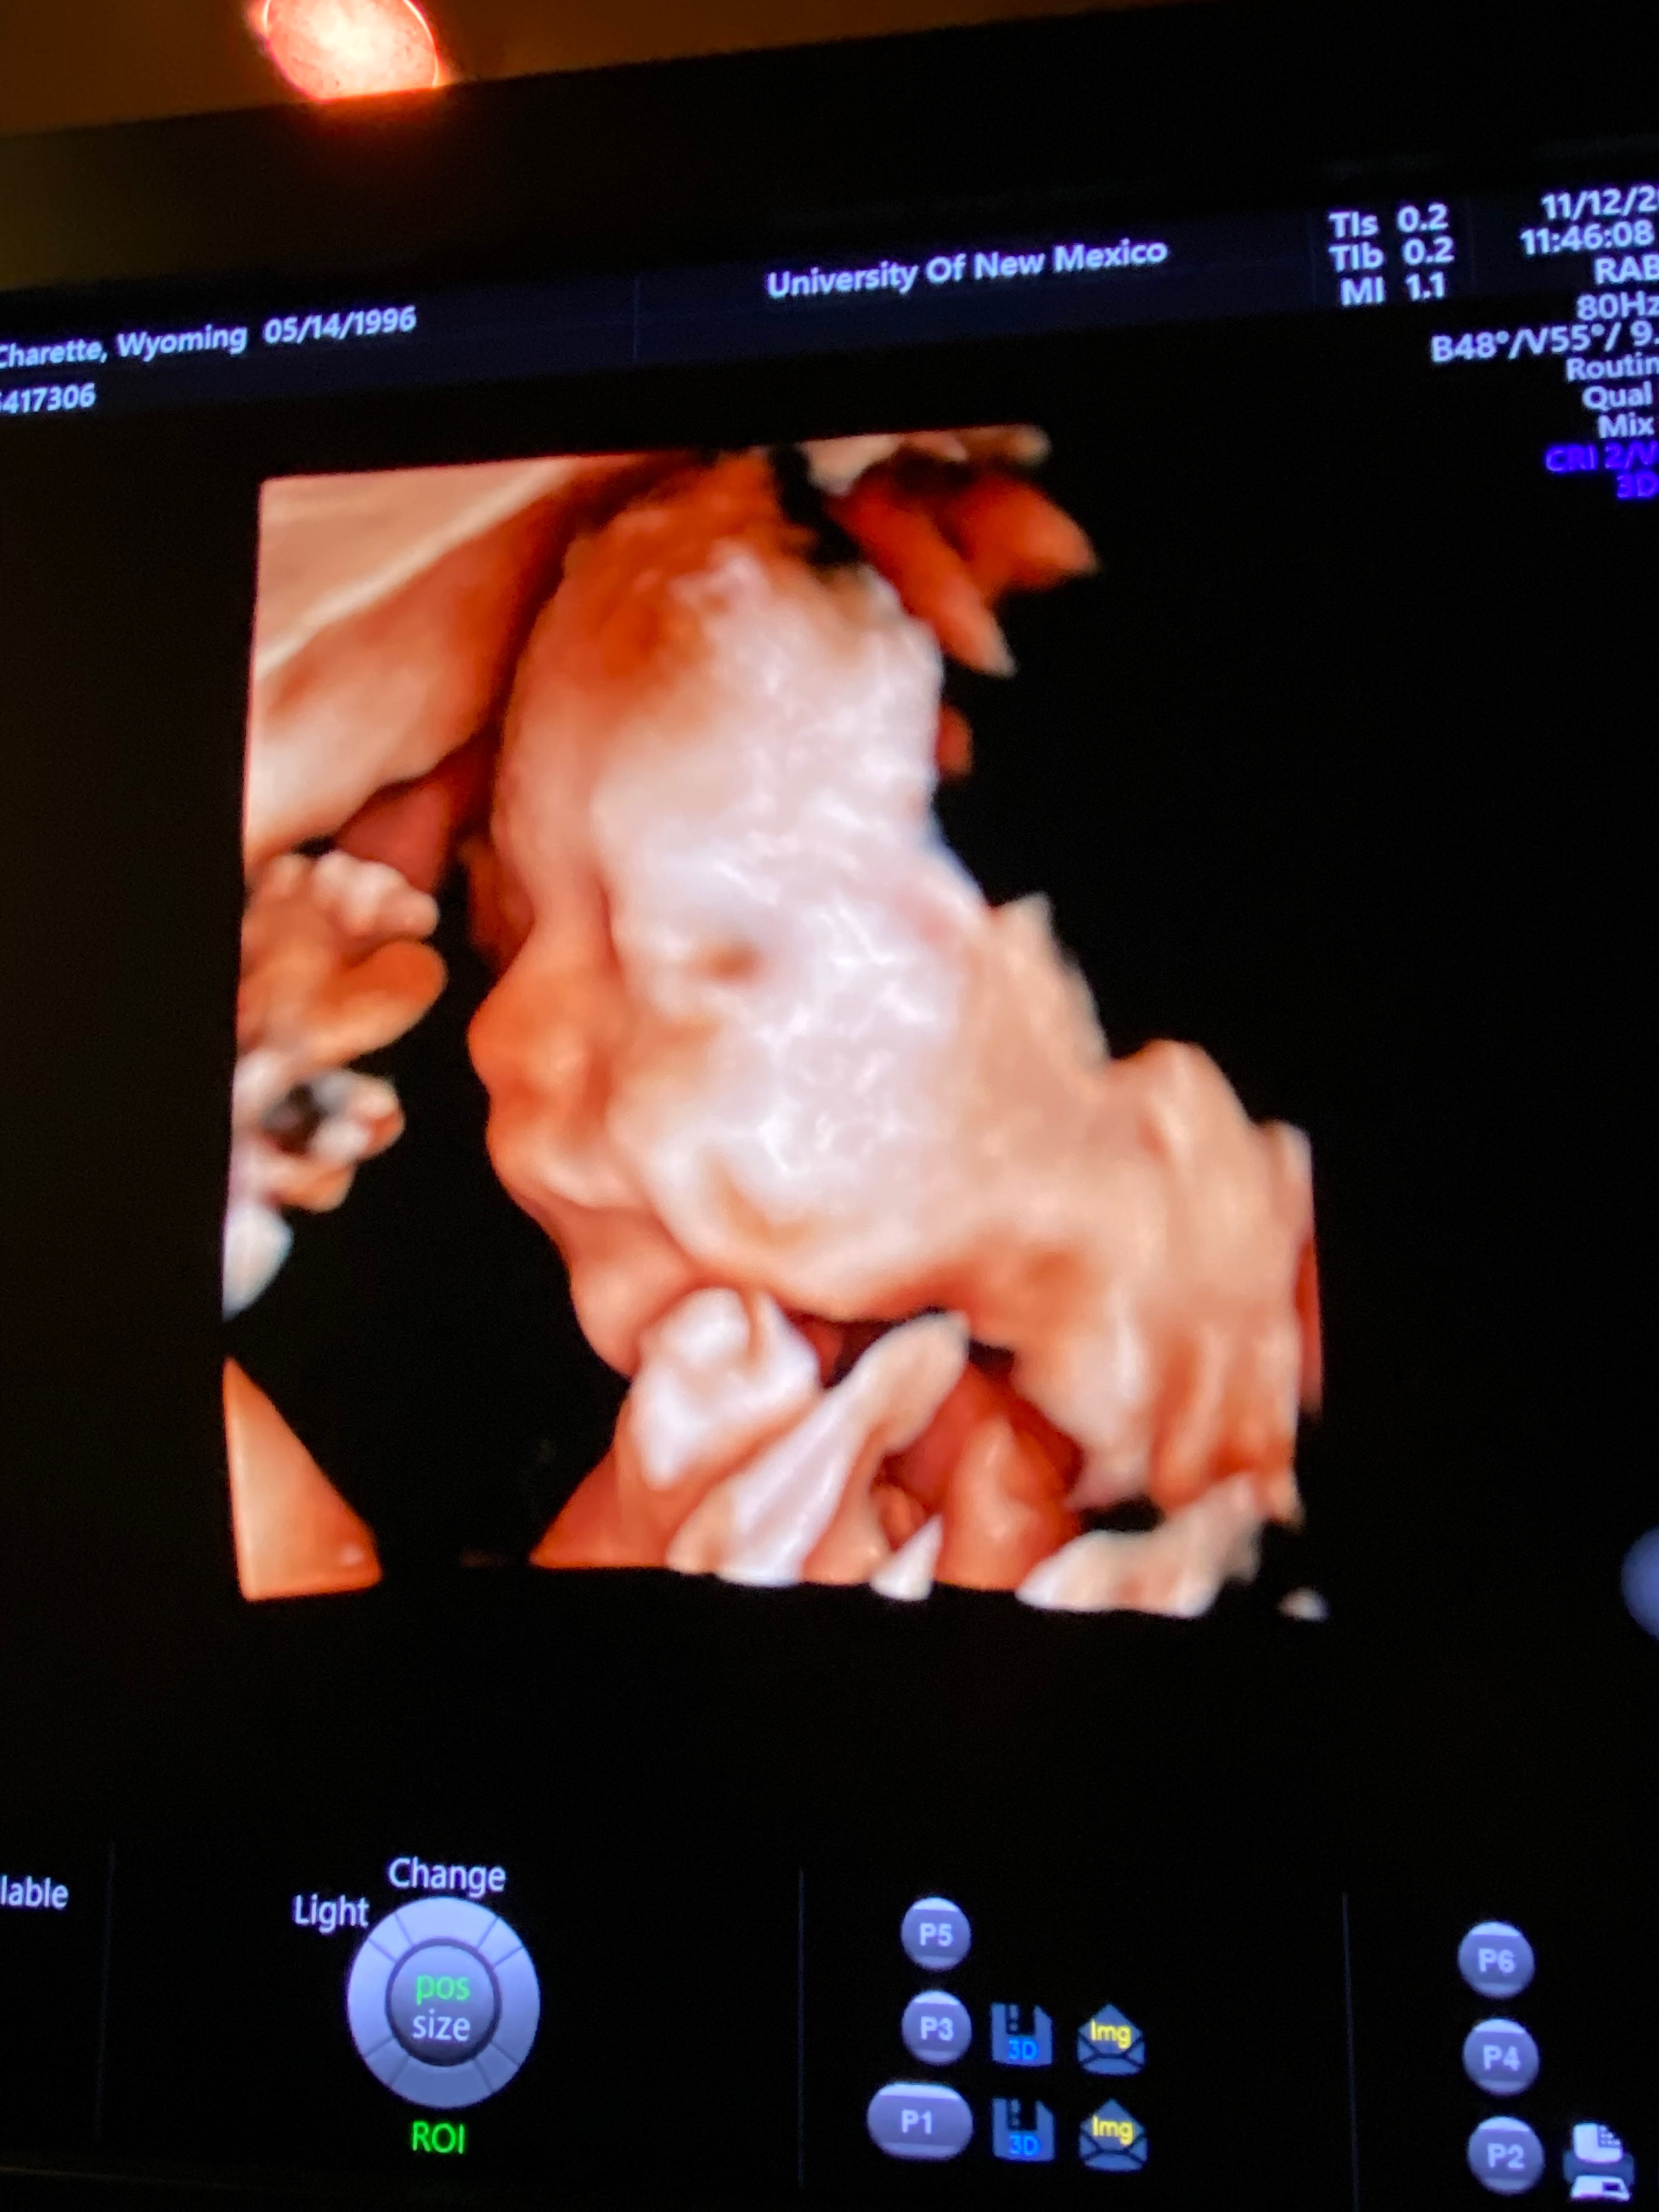

We are reaching out to share our Pregnancy story. My name is Wyoming I’m currently pregnant with my 4th and final baby. This was supposed to be a Happy Journey for my little Family and I.

Only to find out that this joyous occasion comes with unique challenges during my 20week anatomy scan I was told that the doctors couldn’t get good measurements of my Baby’s heart. So I had to get a second opinion done. While at that appointment I was told that my son has been diagnosed with a Rare heart condition known Hypoplastic Left Heart Syndrome (HLHS), a serious congenital heart defect where the left side of the heart is underdeveloped. This condition means that my Baby who we named Altas will require specialized medical care and interventions from the first few days when he is born including open heart surgeries within the first week to ensure he can live a healthy life. But also another open Heart surgery when he is 4 months old. Then another when he turns 4 or 5 years old.